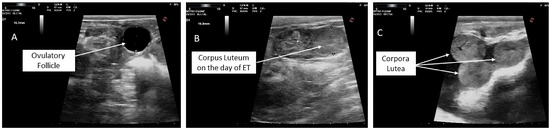

Administration of Human Chorionic Gonadotropin Combined with Phenylbutazone at the Time of Embryo Transfer Synergistically Improves Pregnancy Rates in Dromedary Camels

Effective luteal support is crucial for successful pregnancy following embryo transfer in dromedary camels, highlighting the importance of maintaining adequate luteal function. This study compared three luteal support protocols for pregnancy rates after embryo transfer (ET) in dromedary camels. Recipients with a single [...] Read more.

Effective luteal support is crucial for successful pregnancy following embryo transfer in dromedary camels, highlighting the importance of maintaining adequate luteal function. This study compared three luteal support protocols for pregnancy rates after embryo transfer (ET) in dromedary camels. Recipients with a single ovarian follicle (14~16 mm) were assigned into: (1) untreated control, (2) Phenylbutazone (PBZ) at 3.7 mg/kg IV prior to ET, or (3) human chorionic gonadotropin (hCG) 2000 IU plus 3.7 mg/kg IV PBZ prior to ET. Recipients that showed ovarian inactivity were treated with an injection of 1800 IU of equine chorionic gonadotropin (eCG) after progesterone (P4) priming. Pregnancy was assessed on days 10 (P4 assay) and 60 (transrectal ultrasonography) post-ET. Pregnancy rates on day 10 were higher in the hCG + PBZ (73.3%) and eCG (68.0%) groups than in the PBZ (44.0%) and control (35.0%) groups (p < 0.05). By day 60, the hCG + PBZ group exhibited the highest pregnancy maintenance rate (81.8%) and the lowest embryonic loss rate (18.2%), compared with eCG (53.0%; 47.0%), PBZ (54.5%; 45.5%), and control (57.1%; 42.9%) groups, respectively (p < 0.05). However, there was no significant difference among the eCG, PBZ, and control groups in embryonic loss rates. In conclusion, hCG synergizes with PBZ to enhance corpus luteum function, uterine receptivity, and pregnancy maintenance more effectively than PBZ or eCG. Full article